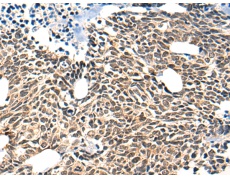

IHC positive control: |

Human liver cancer and Human ovarian cancer |

IHC Recommend dilution: |

30-150 |